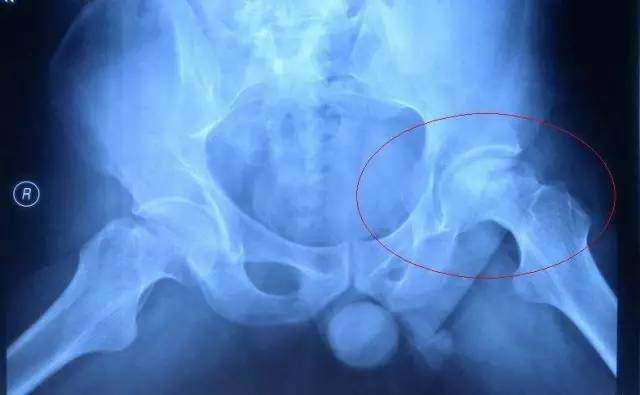

我们先来看一下股骨头坏死三期是什么样儿的:X光片显示股骨头形态改变,可出现边缘不完整、虫蚀状或扁平等形状,骨小梁部分结构消失,骨密度很不均 匀,髋臼及股骨头间隙增宽或变窄,也可有骨赘骨的形成,临床表现疼痛、间歇性的跛行、关节活动受限、患肢有不同程度的缩短等。